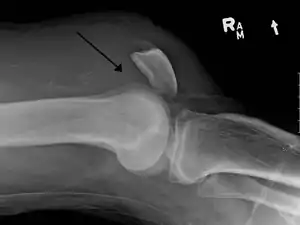

| An x-ray demonstrating quadriceps tendon rupture. Note the abnormal angle of the patella and soft-tissue swelling marked by the arrow. | |